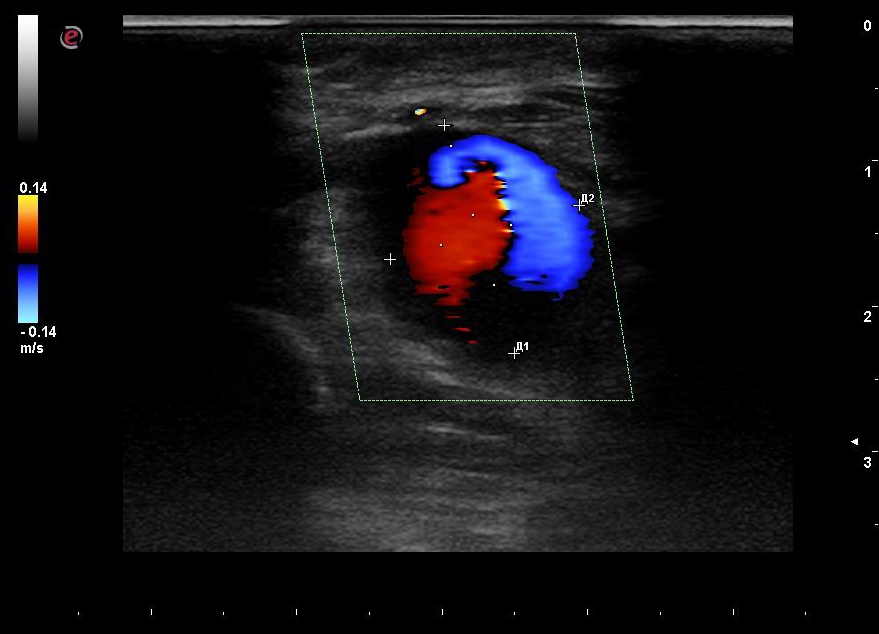

According to duplex scanning of the arteries of the upper limbs: the radial and ulnar arteries are patent, with the main type blood stream through them. The presence of a pseudoaneurysm along the posterior wall of the RA with low-resistance blood flow is noted (Figures 1, 2). The dimensions of the pseudoaneurysm of the RA are 16.4 × 13.5 mm in cross section.

Fig. 2. Duplex scan, color Doppler imaging, cross section. The blood flow in the lumen of the radial artery pseudoaneurysm and its sizes are shown.